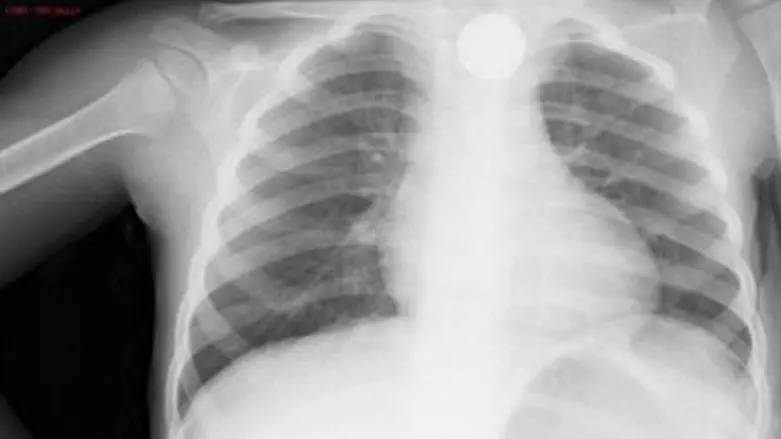

היא הופנתה לחדר המיון בסורוקה ובצילום שבוצע נצפה מטבע שככל הנראה היה בוושט במשך יותר מחודשיים וגרם לכיב משמעותי. המטבע הוצא בחדר ניתוח בפרוצדורה של גסטרוסקופיה.